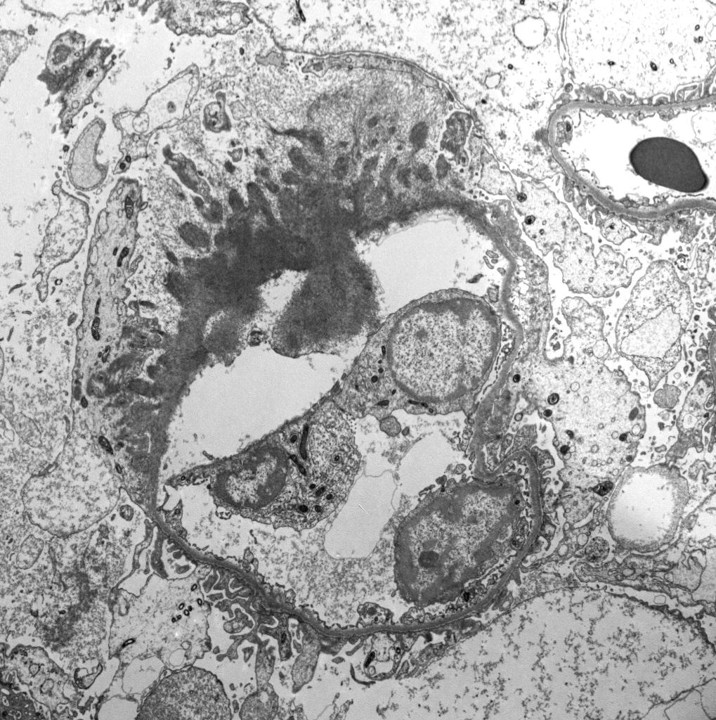

C3 GN in 11 yo boy with proteinuria, hypertension, low C3 (normal C4). EM shows irregular thickening of glomerular capillary wall and mesangial expansion by electron dense deposits. The deposits are somewhat ill-defined with early sign of resorption.